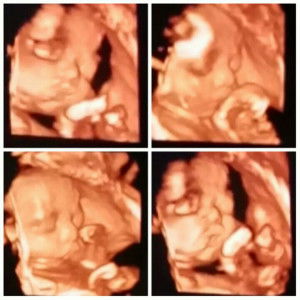

usg

bun wantu UK 34 minggu aku udah USG Dan allhamdulilah hasilnya bagus semua Dari letak Janin,BB Nya ketubannya,plasentanya bagus semua..dan ini UK say a 36-37 bun APA perlu usg lagi ya bun?